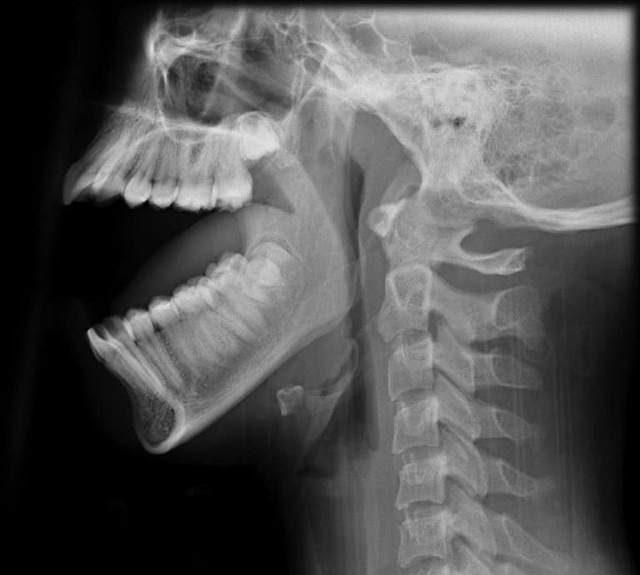

12/06/2024 17:32Thanh niên 27 tuổi trật khớp hàm vì… ngáp: Bác sĩ cảnh báo dấu hiệu nguy hiểm

Ngày 11-6, Trung tâm y tế huyện Phù Ninh (Phú Thọ) cho biết vừa tiếp nhận cấp cứu một nam bệnh nhân 27 tuổi, trú tại xã Bảo Thanh, huyện Phù Ninh, nhập viện sau khi ngáp thì không khép miệng lại được do trật khớp hàm

Sau khi thăm khám, các bác sĩ phát hiện bệnh nhân bị trật khớp thái dương - hàm hai bên.

Ngay lập tức, bệnh nhân được điều trị cấp cứu nắn chỉnh đưa lồi cầu về vị trí chức năng bình thường và băng cố định cằm, đầu, theo dõi trong vòng 1 giờ.

Trao đổi với VnExpress, bác sĩ Đỗ Xuân Hùng, Trưởng khoa Ngoại, Trung tâm Y tế huyện Phù Ninh, cho biết trật khớp thái dương - hàm là sự mất tương quan giải phẫu bình thường giữa lồi cầu xương hàm dưới và lồi khớp xương thái dương. Nếu không điều trị kịp thời, tình trạng này dễ dẫn đến cứng khớp, giãn dây chằng không hồi phục.

Bệnh tiến triển nặng sẽ làm tổn thương khớp thái dương - hàm, gây nhuyễn sụn khớp, thoái hóa và có thể dẫn đến dính khớp thái dương - hàm. Khi đó, các đầu khớp thoái hóa làm dính giữa đĩa khớp với các đầu xương, dẫn đến thủng đĩa khớp.

Trật khớp thái dương - hàm thường do sang chấn đột ngột, há miệng lớn khi ngáp hoặc điều trị răng. Những yếu tố thuận lợi gây tình trạng này là tiền sử chấn thương, dị dạng xương hàm dưới và khớp thái dương rối loạn cắn khớp, giãn dây chằng khớp...

Dấu hiệu trật khớp thái dương - hàm

Theo BSCKI. Vũ Thanh Tuấn (Bệnh viện Đa khoa Medlatec) chia sẻ trên báo Người Đưat Tin, sau một động tác há miệng quá to, nếu hàm bị vẹo sang một bên, miệng khó ngậm lại hoặc không ngậm lại được thì rất có thể bạn đã bị trật khớp thái dương - hàm.

Người trật khớp thái dương – hàm còn có các biểu hiện khác như khó nhai, hay chảy nước bọt, cằm lệch, má một bên hóp - một bên lồi. Có trường hợp cằm nhô ra, má hóp cả hai bên, xuất hiện lồi cầu dưới tai,… Các triệu chứng lâm sàng này khá dễ nhận biết.